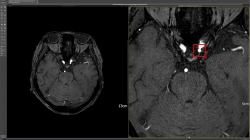

딥노이드(대표 최우식)는 인공지능(AI) 기반 뇌동맥류 검출 진단보조 솔루션 ‘DEEP:NEURO(딥뉴로)’가 건강보험 비급여로 의료기관에서 사용을 시작했다고 24일 밝혔다.딥뉴로는 지난해 식품의약안전처와 보건복지부가 주관하는 혁신의료기기 통합심사 평가를 통해 혁신의료기술로 선정됐다. 이후 국내 17개 병원에 도입을 마쳤고 절차에 따라 한국보건의료연구원에 신고, 실제 사용 허가인 '혁신의료기술 사용 신고(임상진료) 결과 통보'를 받았다. 이에 뇌 MRA 검사 시 환자 동의만 있다면 딥뉴로를 통해 뇌동맥류 검출을 보조 받을 수…